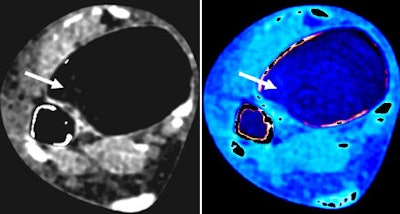

| Gray level-coded (left) and color-coded noncalcium dual-energy CT (right) confirm no bone marrow abnormalities (arrow) and a false-negative result. All images courtesy of Radiology. |